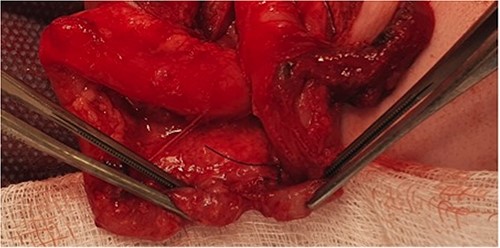

At elective ileostomy closure 2 months later, a colonic stricture was found 5 cm distal to mucous fistula, which was resected. Saline was instilled distal to the excised colonic stricture, which did not progress suggesting further distal obstruction. The decision was made to defer stoma closure at this stage. Subsequent colonoscopy revealed normal distal colon up to the level of the distal transverse colon at which point the colon was completely occluded in a blind ending pouch and on probing with a guide wire no lumen was found. Atresia was confirmed with contrast enema (Fig. 3). At 8 months of age, he underwent laparotomy and resection of a 10 cm section of transverse colonic atresia. Histology reported narrowing of the transverse colon, focal granulation tissue, and mucosal web formation. His recovery and subsequent follow-up have been uneventful.

Contrast enema for case 2 showing complete failure of passage of contrast into distal transverse colon.